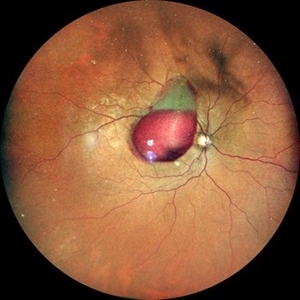

Old Supero-Temporal Branch Retinal Vein Occlusion with Macular Hole Right Eye Fundus

Fundus photograph of a 36-year-old female presented with supero-temporal branch retinal vein occlusion with macular hole in right eye.

Photographer: Dr. Akansha Sharma-Retina Foundation

Condition/keywords: branch retinal vein occlusion (BRVO), macular hole